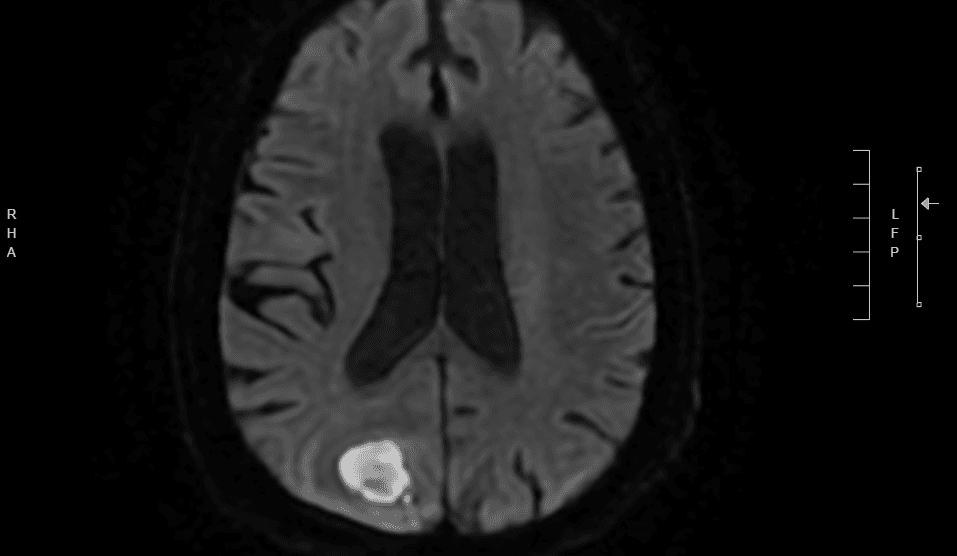

Laboratory studies show WBC 14,200 cells/mcL with 82% neutrophils, CRP 68 mg/L, and ESR 72 mm/hr. Blood cultures are drawn. CT brain with contrast reveals a 3.2-cm ring-enhancing lesion in the right parietal lobe with surrounding vasogenic edema and 4 mm of midline shift. MRI with diffusion-weighted imaging confirms marked restricted diffusion within the lesion, as shown below. Chest CT obtained to evaluate the prior lung process reveals a 3.5-cm cavitary lesion in the posterior right lower lobe with an air-fluid level consistent with lung abscess. HIV antigen-antibody test is negative. Serum Cryptococcal antigen and Toxoplasma IgG are negative.

Diffusion-weighted MRI (DWI): restricted diffusion within a right parietal ring-enhancing lesion.